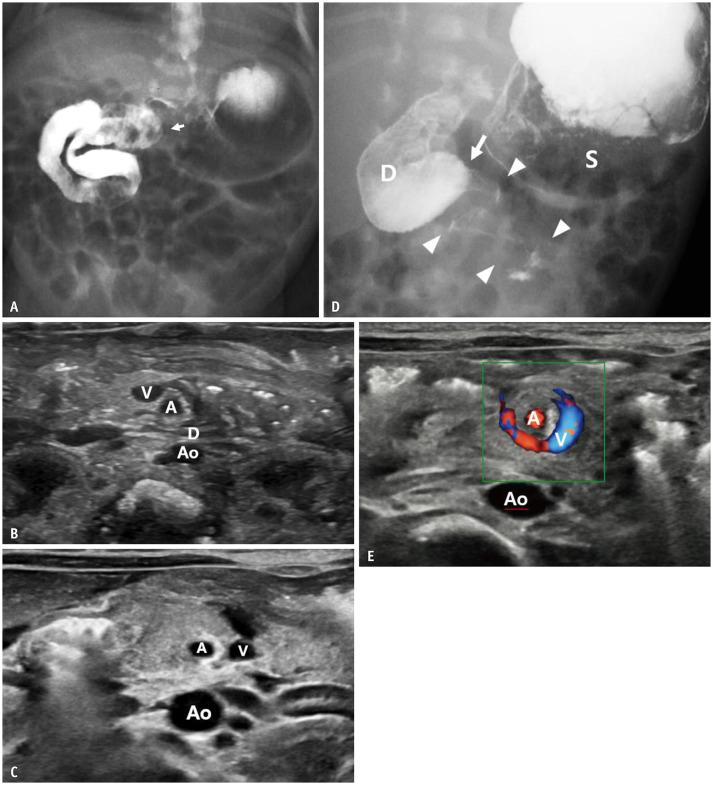

Gastrointestinal (GI) emergencies in neonates and infants encompass from the beginning to the end of the GI tract. Both congenital and acquired conditions can cause various GI emergencies in neonates and infants. Given the overlapping or nonspecific clinical findings of many different neonatal and infantile GI emergencies and the unique characteristics of this age group, appropriate imaging is key to accurate and timely diagnosis while avoiding unnecessary radiation hazard and medical costs. In this paper, we discuss the radiological findings of essential neonatal and infantile GI emergencies, including esophageal atresia and tracheoesophageal fistula, hypertrophic pyloric stenosis, duodenal atresia, malrotation, midgut volvulus for upper GI emergencies, and jejunoileal atresia, meconium ileus, meconium plug syndrome, meconium peritonitis, Hirschsprung disease, anorectal malformation, necrotizing enterocolitis, and intussusception for lower GI emergencies.

新生儿和婴儿的胃肠道(GI)急症涵盖了从胃肠道的开始到结束的各个方面。先天性和后天性疾病都可能导致新生儿和婴儿出现各种胃肠道急症。鉴于许多不同的新生儿和婴儿胃肠道急症的临床发现具有重叠或非特异性,以及该年龄段的独特特征,适当的影像学检查对于准确和及时的诊断至关重要,同时避免不必要的辐射危害和医疗费用。在本文中,我们讨论了基本的新生儿和婴儿胃肠道急症的放射学表现,包括食管闭锁和食管气管瘘、肥厚性幽门狭窄、十二指肠闭锁、肠旋转不良、胃上消化道急症,以及空肠回肠闭锁、胎粪性肠梗阻、胎粪栓综合征、胎粪性腹膜炎、先天性巨结肠、肛门直肠畸形、坏死性小肠结肠炎和肠套叠等下消化道急症。